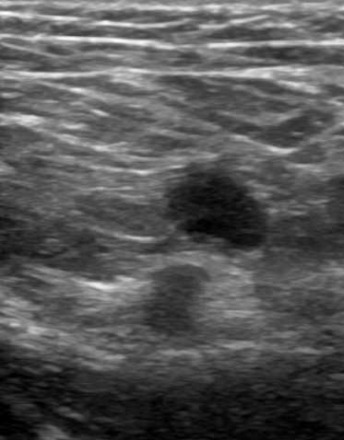

A case of sentinel node-negative breast cancer with axillary lymph node recurrence 10 years after surgery